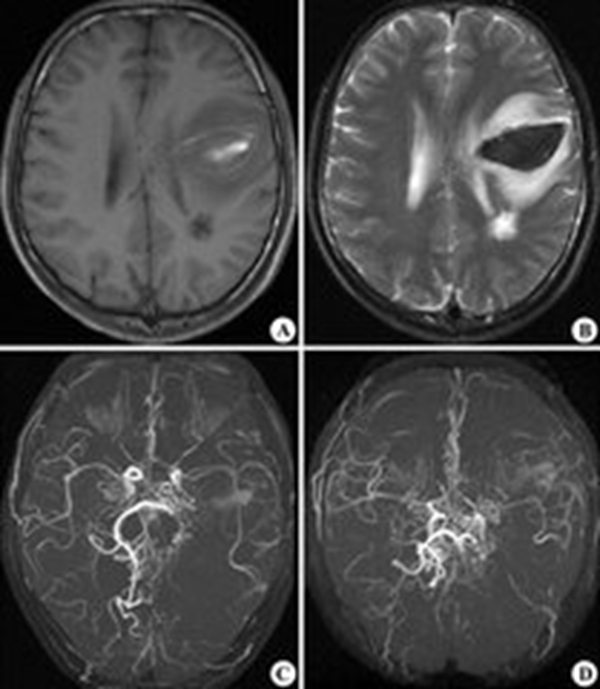

煙霧病造影表現

煙霧病造影圖

煙霧病造影

煙霧病血管造影